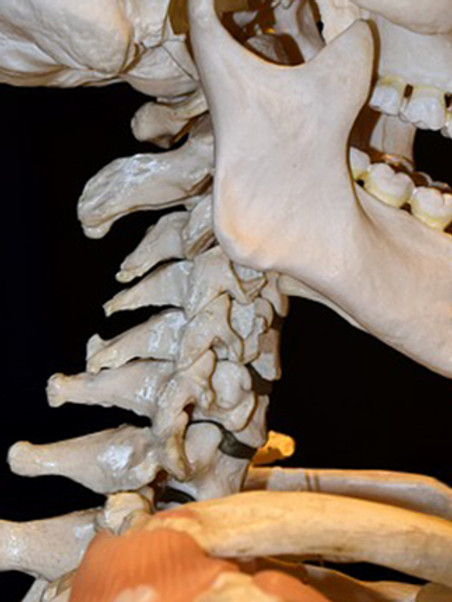

우선 목디스크란 목뼈 사이의 디스크가 손상되어 발생하는 질환을 의미합니다. 디스크는 척추뼈 사이에서 충격을 흡수하고 신경을 보호하는 역할을 하는데, 디스크가 손상되면 신경이 압박되어 통증, 저림, 마비 등의 증상이 나타납니다.

목디스크의 원인은 다양하지만, 가장 흔한 원인은 외상입니다. 외상은 교통사고, 스포츠 부상, 낙상 등 다양한 원인으로 발생할 수 있습니다. 또한, 잘못된 자세, 과도한 스트레스, 노화 등이 목디스크의 발생 위험을 높입니다.

목디스크의 증상은 다양하며 환자마다 그 증상이 다르게 나타날 수 있습니다. 가장 흔한 증상은 목의 통증입니다. 목의 통증은 목 뒤쪽, 어깨, 팔, 손까지 뻗쳐서 나타날 수 있습니다. 또한, 저림, 마비, 감각 이상, 손발의 힘 저하 등의 증상이 나타날 수 있습니다.